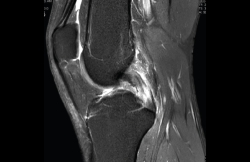

4.3. Osteocondritis

En la osteocondritis se aprecia una lesión subcondral caracterizada por resorción ósea, colapso y la formación de un secuestro.

El estudio por RM es una herramienta valiosa para diagnosticar e identificar las lesiones del cartílago. Conocer el aspecto del cartílago y saber cuánto y cuándo se lesiona, basándose en las clasificaciones actuales, permiten al radiólogo proporcionar la máxima información al clínico(20).

Figura 53. Corte de secuencia sagital (A) y axial (B) T2 Fat-Sat de RM de rodilla: lesiones osteocondrales en el fémur y la rótula.

Numerosos estudios demuestran la utilidad de la RM para definir la estabilidad o inestabilidad de la lesión en la osteocondritis, destacando su carácter no invasivo y la capacidad de valorar la progresión y la respuesta al tratamiento(21)(Figuras 53 y 54).